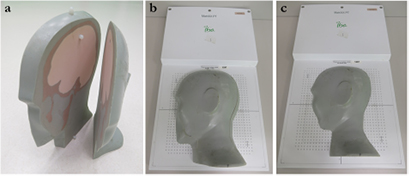

After the preliminary validation of the simpler dose distributions in water, an anthropomorphic phantom was taken into account. The phantom has the same characteristics as described by Albertini et al (2011). Briefly, it consists of five different tissue substitute materials simulating different tissue types and it is cut into sagittal planes. To simulate shallow targets, the most superficial slabs of the phantom (i.e. 1/6 and 2/6 of the head, because the head is divided in six parts) were considered and a 2D ionization chamber array detector was placed underneath the phantom (figure 1 and 2). The detector consists of a 1020 vented ion chamber array arranged in a 32 × 32 grid with the exception of the four corner position (MatriXX PT, IBA Dosimetry GmbH). The distance between the individual chambers is 7.62 mm center-to-center, and the diameter of each ion chamber is 4 mm.

Figure 1. Two outer slabs of the head phantom (a). Two experimental configurations were considered: the two slabs were placed together (i.e. 2/6 of the head) on the 2D ion chamber (b) or just the most superficial one (i.e. 1/6 of the head) was considered (c).